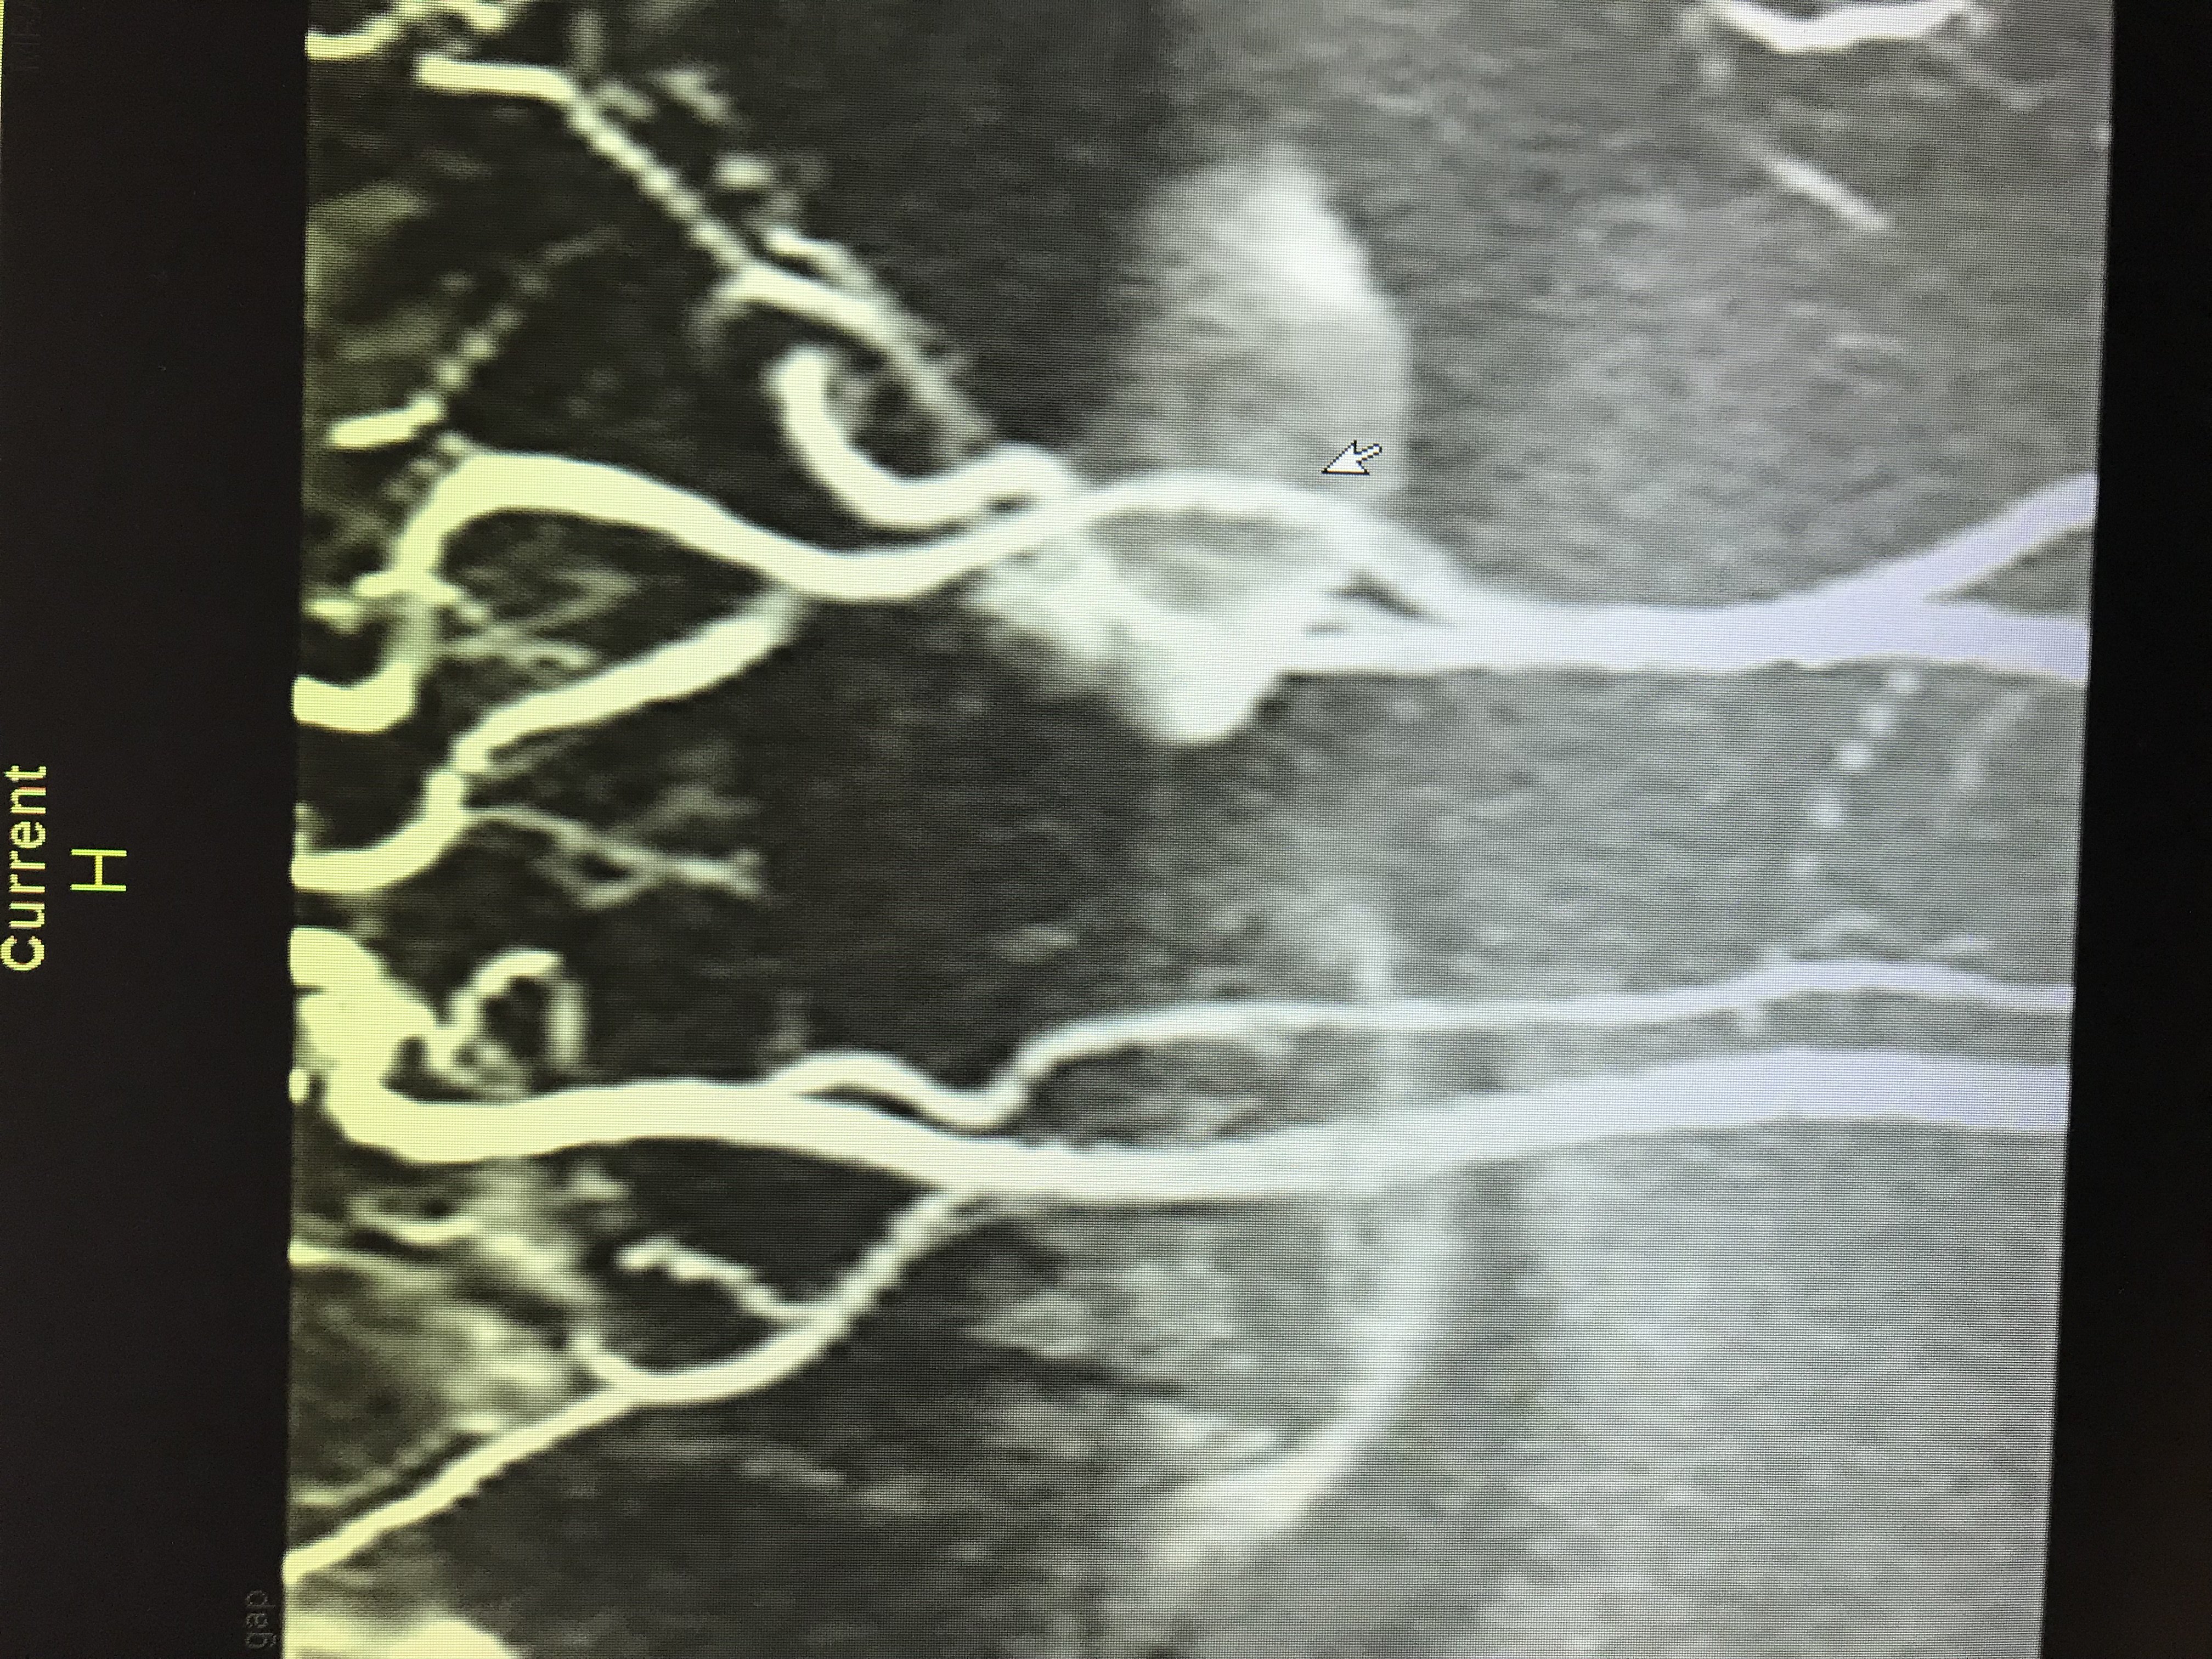

Discussion: This is a case of 49 year old Caucasian female patient with known past medical history of hypothyroidism who presented to the hospital emergency department with sudden onset of visual disturbances, severe headache, numbness and tingling sensation of her left arm. On further questioning, she described her visual disturbances of having black and silver floaters scattered throughout her visual field associated with pulsatile tinnitus and whooshing sensation in her ears. On physical exam, the National Institutes of Health stroke scale (NIHSS) was 0 on admission. CT head without contrast showed no evidence of acute intracranial hemorrhage or infarction. CT angiography showed narrowing of the right V4 segments of the vertebral artery along with beaded appearance of proximal left ICA suspicious for Fibro-muscular Dysplasia with no evidence of aneurysm, carotid or vertebral artery dissection. MRA abdomen was done which showed no involvement of the renal arteries. Neurosurgery evaluated the patient and recommended continuing aspirin, statin and follow-up as outpatient for close monitoring.